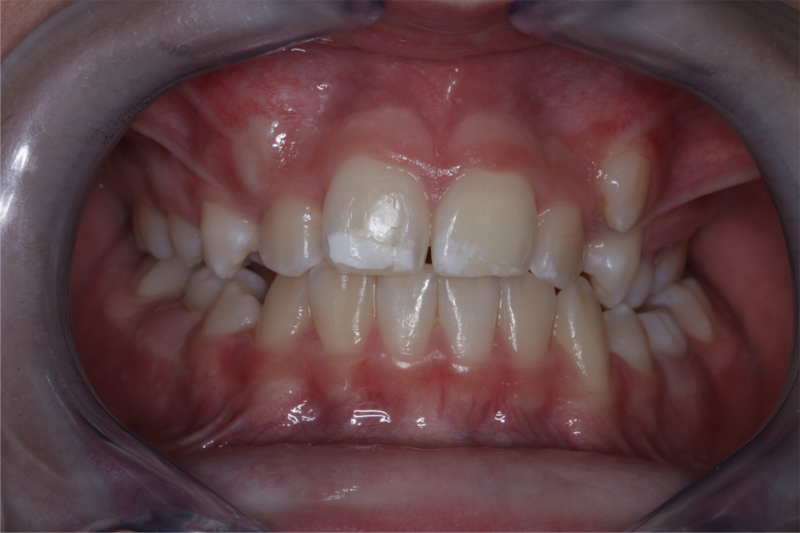

Er was veel te weinig ruimte voor de hoektanden.

Het ruimtegebrek voor de hoektanden is duidelijk.

De getransplanteerde hoektanden staan nu op de plek van de snijtanden.

Eindresultaat na het opbouwen van de hoektanden, zodat deze er uit zien als snijtanden.